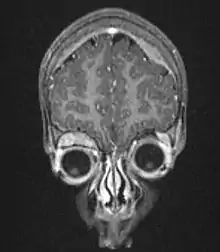

على الفحص المجهري، توصف الخلايا السرطانية عادة بأنها صغيرة ومستديرة وزرقاء، ويمكن مشاهدة نماذج الوريدة (نموذج هومر رايت للوريدات الزائفة). الوريدات الزائفة هومر رايت، هي خلايا الورم حول القرص العصبي، ولا ينبغي الخلط بينها وبين الوريدات الحقيقية (فليكسنر – وينتر ستينر), هذه الوريدات[24] هي خلايا الورم حول الأوعية الدموية وغالبا ما تشاهد في اورام أرومة الشبكية.[25] وهي أيضا متميزة عن الوريدات الزائفة من الورم البطاني العصبي والتي تتكون من خلايا الورم مع البروتين الدبقي الليفي الحمضي (GFAP)--العمليات الايجابية تهوي باتجاه الاوعية الدموية (وبالتالي مزيج من الاثنين معا).[26] وتستخدم مجموعة متنوعة من الصبغات الكيميائية النسيجية المناعية من قبل خبراء الأمراض لتمييز ورم الخلايا البدائية العصبية من المحاكاة النسيجية، مثل الساركومة العضلية المخططة وسرطان الغدد الليمفاوية وساركومة يوينغ وورم ويلمز. في شباط 2007، أعلنت تقنيات ألثيا تطوير القدرة على التشخيص الجزيئي للتمييز بوضوح بين أنواع مختلفة من سرطانات الطفولة، ووضعت بالتعاون مع المعهد القومي الأميركي للسرطان (NCI).[27]